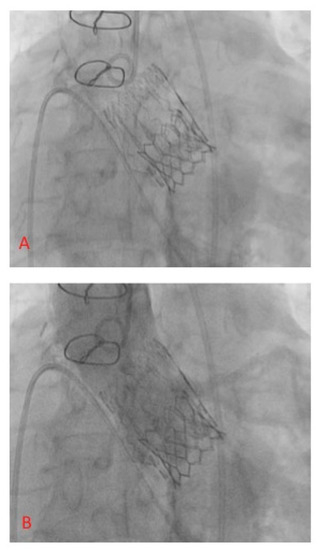

2.2. Technology

2.3. VIV-TAVR Planning and Technical Procedures